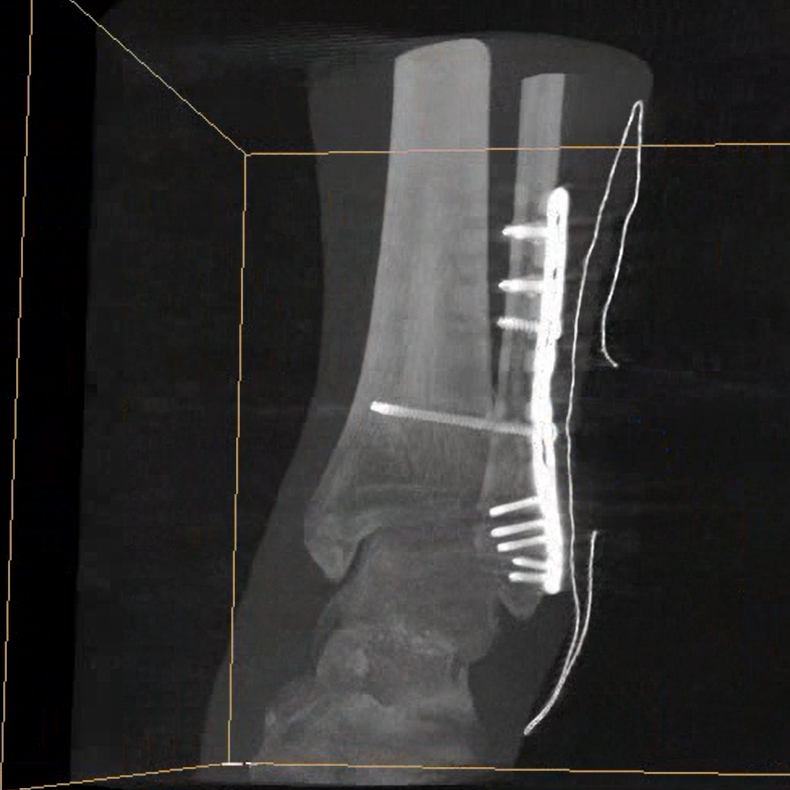

術(shù)中三維成像和橫斷面圖像提供多角度的手術(shù)診斷信息,輔助醫(yī)生進(jìn)行術(shù)中評估判斷,諸如骨折復(fù)位情況和內(nèi)植入螺釘?shù)某叽绾臀恢茫o助手術(shù)更好地完成。

平板垂直升降運動 便于術(shù)中微調(diào)平板與拍攝主體的距離,更加貼近病灶體,成像范圍更大,圖像更清晰。